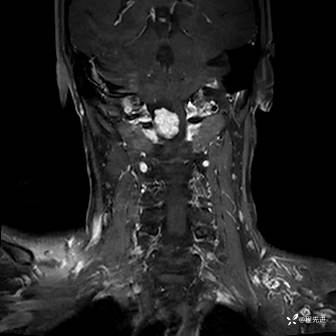

MRI平扫+增强:

T1增强: